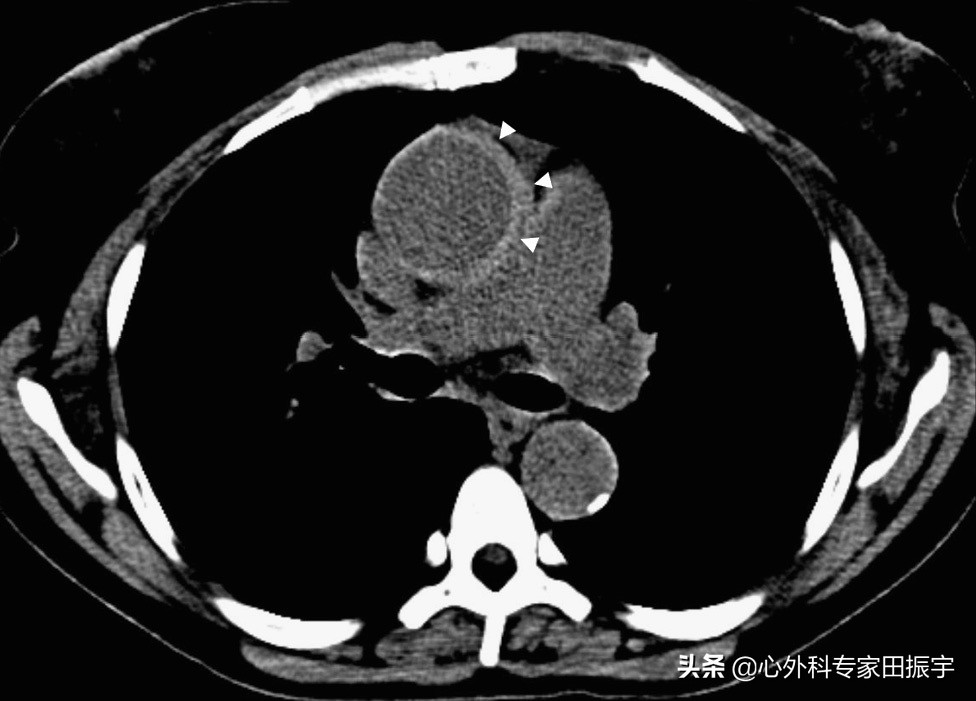

主动脉壁间血肿

图5 在一名45岁女性胸痛,可疑主动脉夹层,胸部平扫轴向CT图像显示,一种A型主动脉壁间血肿(箭头)厚度为6毫米。